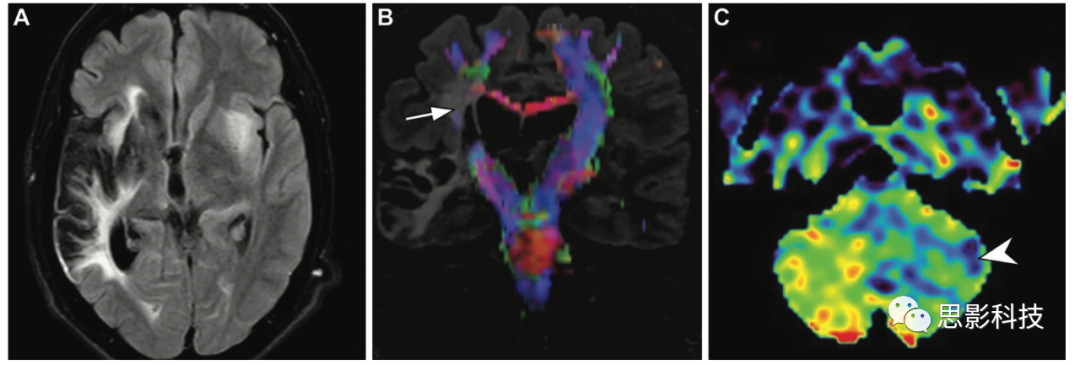

一例5歲兒童心臟手術(shù)后發(fā)生急性缺血性卒中。(A)軸位彌散加權(quán)磁共振成像未顯示患者運(yùn)動(dòng)功能障礙后立即發(fā)生缺血性卒中的證據(jù)。(B)磁共振血管造影顯示左側(cè)頸內(nèi)動(dòng)脈信號(hào)減弱,提示閉塞和左側(cè)頸動(dòng)脈相對(duì)較差的側(cè)支血管(箭頭)。(C)ASL MRI顯示廣泛的低灌注,幾乎整個(gè)左半球的腦血流量減少,表明有危險(xiǎn)的組織和動(dòng)脈傳輸偽影,其表現(xiàn)為左側(cè)sylvian池波形線性高信號(hào)強(qiáng)度,這是由于左側(cè)大腦動(dòng)脈持續(xù)標(biāo)記的自旋(箭頭)

(D)24小時(shí)后獲得的軸位增強(qiáng)CT圖像證實(shí)了廣泛的缺血性卒中,遍及整個(gè)左側(cè)頸動(dòng)脈。